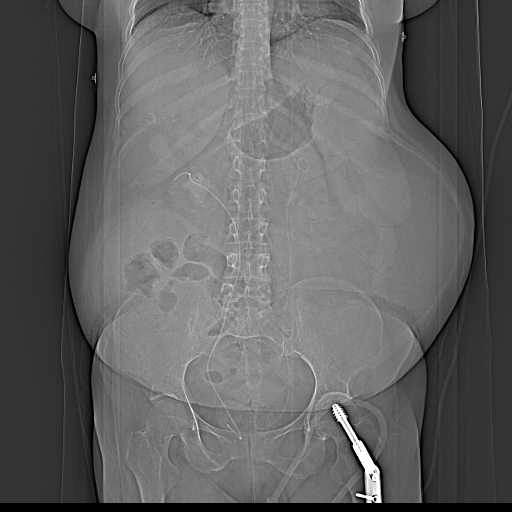

Sỏi niệu quản (Ureteric calculi)